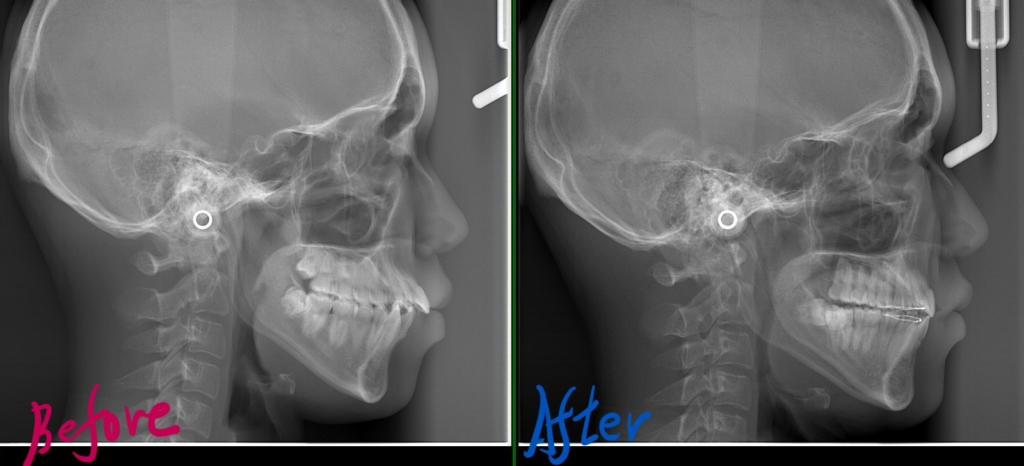

レントゲン写真で確認すると、

この患者さんの場合、

レントゲン写真でも比較してみましょう

矯正治療により、きれいな歯並びと良い噛み合わせを獲得することが出来ました。

口元も当初の予想以上にスッキリさせることが出来ました。